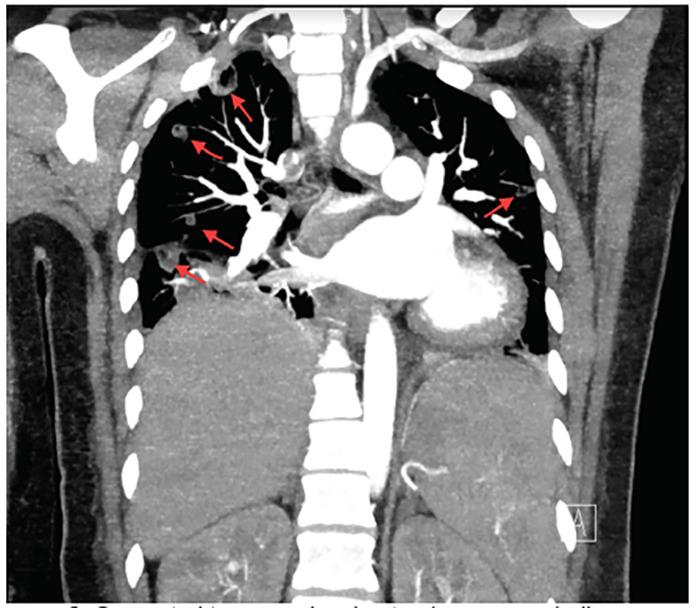

A 27-year-old female presented with left-sided neck swelling and erythema. Computed tomography noted left anterior jugular vein thrombophlebitis and multiple cavitating foci, consistent with septic emboli. We report a rare case of Lemierre syndrome in which the thrombus was found in the anterior jugular vein, as opposed to the much larger internal jugular vein more traditionally associated with creating septic emboli.

一名27岁女性出现左侧颈部肿胀和红斑。计算机断层扫描显示左颈前静脉血栓性静脉炎和多个空洞灶,与脓毒性栓子相符。我们报告一例罕见的勒米尔综合征病例,其中血栓位于颈前静脉,而非更传统地与产生脓毒性栓子相关的大得多的颈内静脉。